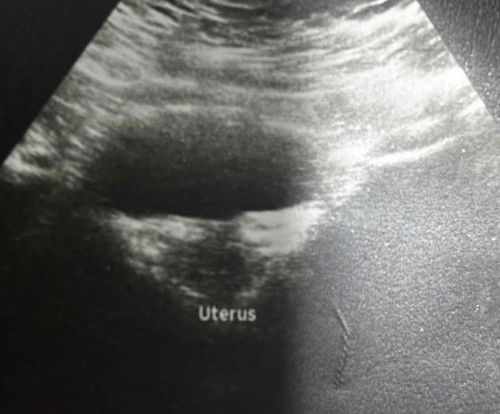

Adakah ini keguguran 🥲 last period 10oct .. hari ni tiba2 period balik keluar macam ini ..

Hi mommies, I baru2 ni ada pergi scan. Dr cakap kantung dah takda during my 8w scan tapi last I pergi scan 5 weeks kantung ada dah. Last period 12 Sept, light spotting 12 Oct (three days) & i nak tahu bulatan hitam dalam hijau itu apa? 😅